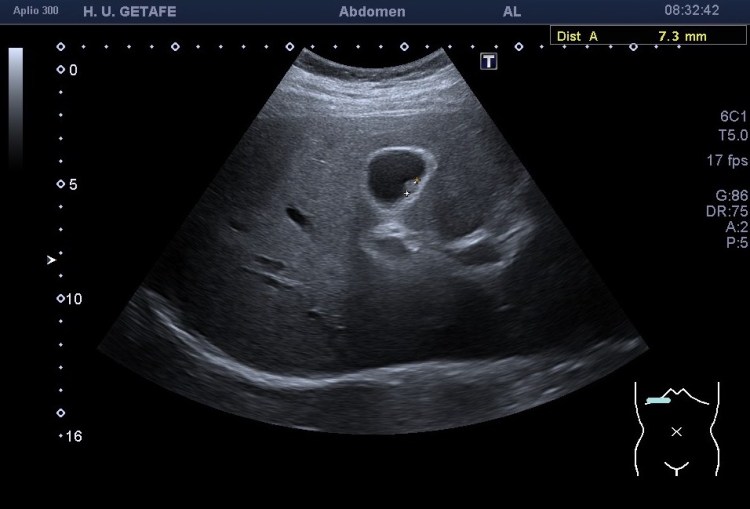

283. Pólipo vesicular. Zoom.

El pólipo vesicular es uno de los hallazgos ecográficos más comunes que tenemos en la ecografía abdominal. Para estudiar bien la vesícula debemos tener al paciente en ayunas con el fin de que la vesícula esté bien distendida, que esté plegada dificultaría notablemente la localización de este tipo de patologías.

Son estructuras redondeadas pegadas a la pared vesicular hiperecogénicas. Normalmente única, pueden aparecer en número variable lo que se conoce como una poliposis vesicular

Características semiólogicas básicas:

Los pólipos de colesterol son los más frecuentes.

Parecen masas adyacentes a la vesícula.

No presentan sombra posterior.

No se mueven al cambiar de posición al paciente.

El diagnóstico diferencial pueden ser la litiasis vesiculares, que son móviles, y que suelen dejar sombra acústica posterior.

El estudio del pólipo tras su localización se realiza en dos proyecciones, variando al paciente de posición para ver si se mueve. Ponemos doppler, tanto color como modo angio, con el objetivo de demostrar un vaso en el interior del pólipo, que lo delataría como una estructura de aspecto maligno y debería ser valorado por el radiólogo y por el cirujano convenientemente. Por eso ajustar el doppler es muy importante en este caso también.

Medimos para hacer seguimiento de la lesión si se requiriese así. Aplicamos zoom para estudiarlo detalladamente, a mi me encantan las imágenes en este Canon. El Zoom es muy bueno y el estudio del pólipo gana muchísimo. Hablando del Zoom…

Como muy bien puedes observar el caso es bastante anodino, las imágenes te las he puesto y son la excusa para explicarte el uso del Zoom. Habitualmente es un ajuste ecográfico que no usamos en exceso, solo puntualmente, puede pixelar en exceso la imagen, como cuando hacemos una foto con nuestro móvil y la ampliamos con el gesto de nuestros dedos…pixelamos la imagen, perdemos resolución, pero lo nuevos equipos, ganan en esto también y con las sondas de baja frecuencia podemos conseguir imágenes muy bonitas de alguna ecoestructura pequeña y que nos interese medir bien, y este caso me resultó muy plástico y te lo quería explicar. Repasamos el concepto de pólipo vesicular y lo enlazamos con el uso del zoom.